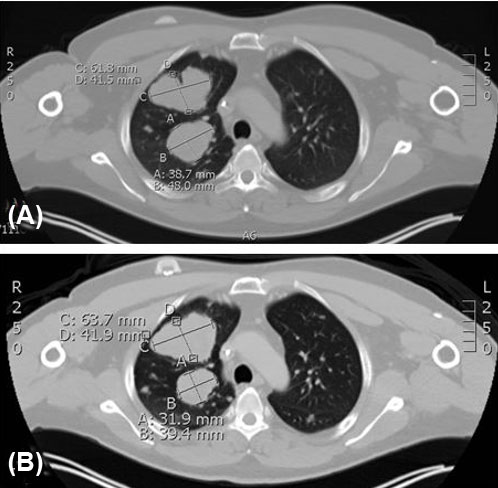

Figure 5: Right upper lobe lung mass stability from March 2021 to May 2021 while on nivolumab and cabozantinib. (A) March 2021 chest CT with right anterior mass measuring up to 61.8 41.5 mm and right posterior mass measuring up to 38.7 × 48.0 mm. (B) May 2021 chest CT with right anterior mass measuring up to 63.7 × 41.9 mm and right posterior mass measuring up to 31.9 × 39.4 mm.

Considering his PD-L1 tumor portion score of 30%, nivolumab was initiated. Shortly after, interval CT showed possible progression in size of pulmonary nodules, prompting the addition of cabozantinib. The patient had minimal side effects on combination nivolumab and cabozantinib only to include palmar plantar erythrodysesthesia that was well managed with topical emollients and steroids. Positron emission tomography-computed tomography imaging showed partial/mix response of dominant pulmonary nodules, but mediastinal lymph nodes reduced by greater than 30% (Figure 5). He achieved disease stability on combination nivolumab/cabozantinib therapy with symptomatic improvement of cough and shortness of breath up to nine months before disease again progressed. He was trialed briefly on one cycle of regorafenib with poor tolerance and no benefit, therefore he transitioned electively to hospice care.